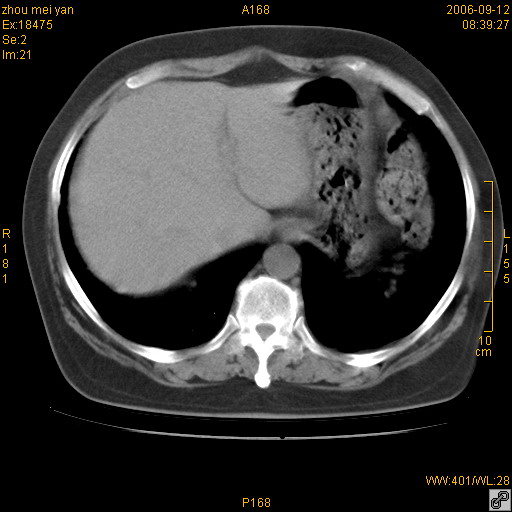

患者、女、55岁。因心率失常住院检查ct发现胸部多发结节。腹部b超肝、胆、胰、脾、肾、子宫附件未见异常。无结核病史,无粉尘接触史。请大家来会诊。谢谢!

病变位于胸膜,多发结节,边界清楚,内见小结节状钙化。其它未见异常。

双侧胸膜多发结节,形态不规则,边缘较清楚,每一个结节中心似乎都有钙化点的特征,与胸膜广基相切。临床无结核病史,无粉尘接触史。

胸膜间皮瘤可能性大。在气管隆突前可见一肿大淋巴结影。

感染性肉芽肿,双侧膈底胸膜见多个结节灶,内见斑点状钙化,有否疫水接触史